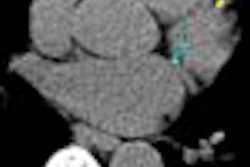

In general there are three ways to utilize CT during PET/CT: a noncontrast CT for attenuation correction and localization, a noncontrast CT followed by PET and then contrast-enhanced CT, or an enhanced CT as part of the PET/CT, Blodgett said.

Performing PET/CT with a single contrast-enhanced CT offers less radiation exposure to the patient than doing two CT scans, Blodgett said. Sites can charge for CT as usual. However, users must be aware of the pitfall of attenuation artifacts, he said.

Another approach, PET/CT with low-dose noncontrast CT and a full-dose contrast-enhanced CT, allows for use of low-dose CT for attenuation correction to avoid artifacts, but provides increased radiation dose to the patient, Blodgett said.

For example, a nuclear medicine physician might read a PET/CT and miss a non-FDG-avid tumor on the CT portion of the exam.